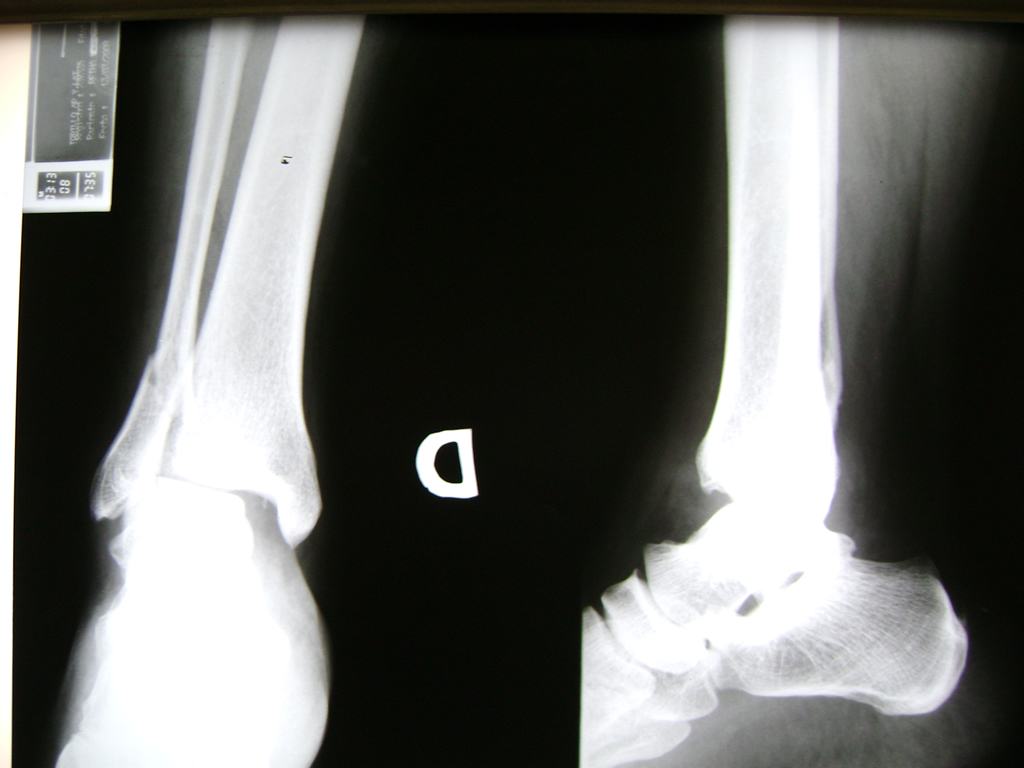

Una fractura de tobillo es la rotura de uno o más de los huesos del tobillo. Estas fracturas pueden ser:

- Los extremos de los huesos están desalineados entre sí (desplazados).

- La fractura se extiende hasta la articulación del tobillo (fractura intra-articular).